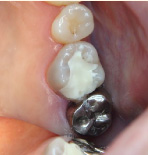

下の写真の一番左は実は治療前の写真です。痛みもなく一見問題なく入っている銀歯も除去してみると中に虫歯が。殺菌作用のある薬を詰めて治療中です。外からは分かりずらい虫歯も多いので定期検診がおすすめです。

- 治療前

- 除去

- 治療中